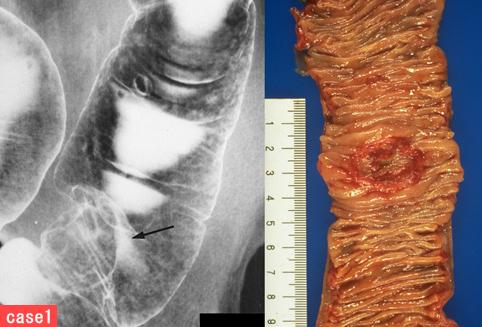

部位(按器官分)大肠/降结肠

检查方法X线

肿瘤的肉眼分类2型(溃疡局限型)/

肿瘤最大直径25~29